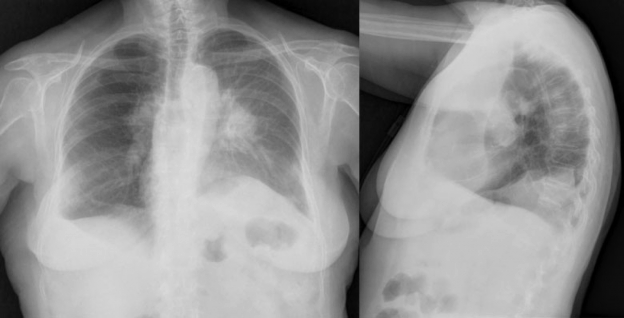

Presentamos el caso de una mujer de 72 años con antecedentes de carcinoma ductal infiltrante de mama en remisión seis años antes, que acudió a urgencias por dolor torácico, disnea y tos seca persistente. Tenía una angiografía coronaria reciente normal y los análisis de laboratorio revelaron como valor destacable un dímero-D de 742 µg/l. Con esos datos se solicitó desde el servicio de urgencias una angio-TC de arterias pulmonares (►Fig. 1) donde se apreciaba un voluminoso defecto de repleción en la arteria pulmonar derecha que se diagnosticó como TEP. La paciente fue anticoagulada y controlada con mejoría inicial, pero cuatro meses después volvió a urgencias con empeoramiento de la disnea, tos y hemoptisis. En las radiografías de tórax (►Fig. 2) se apreciaba un aumento de tamaño de arterias pulmonares con una masa parahiliar izquierda y atelectasia completa de lóbulo superior izquierdo (LSI), mejor valorados en la angio-TC torácica (►Fig. 3), donde persistía la ocupación arterial con unas características que, unidas a su evolución, sugirieron un origen tumoral. Se realizó biopsia a través de broncoscopia de la masa que obstruía el bronquio del lóbulo superior izquierdo, con un resultado histológico de sarcoma intimal de arterias pulmonares (►Fig. 4), patología muy poco frecuente y de difícil diagnóstico diferencial con el TEP.

Radiografías posteroanterior (izquierda) y lateral de tórax (derecha) en las que se aprecia un aumento de tamaño de las arterias pulmonares y una masa parahiliar izquierda que sugiere ser la causa del colapso completo de lóbulo superior izquierdo, demostrado por la pérdida de volumen, el desplazamiento de la cisura mayor, del bronquio principal izquierdo y la elevación del hemidiafragma así como por el aumento de la atenuación respecto al lado contralateral. Hay leve derrame pleural bilateral asociado.